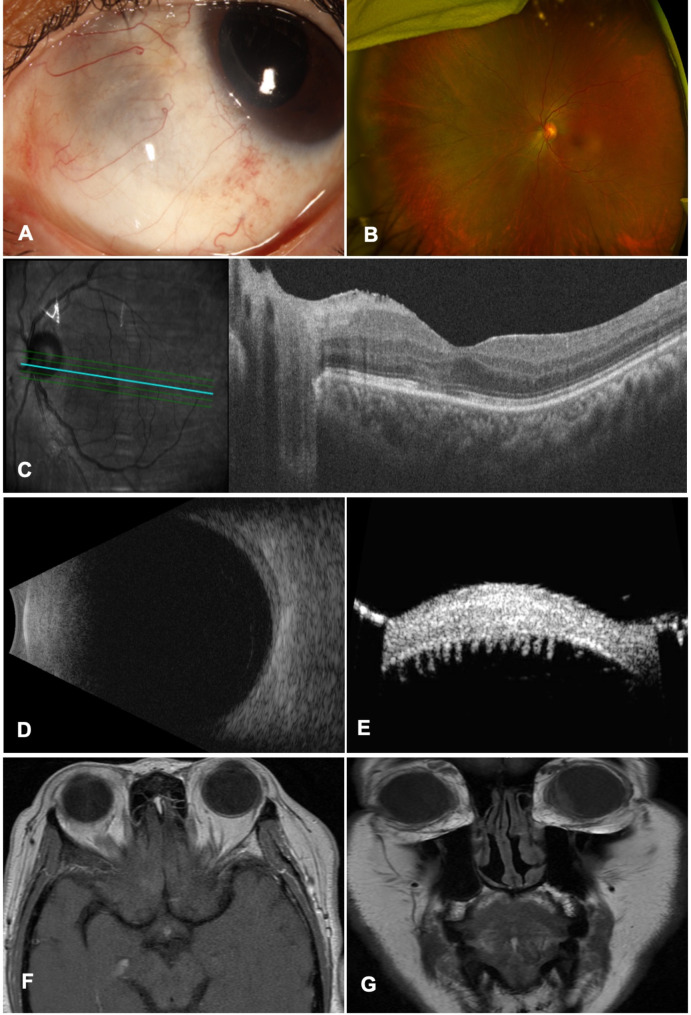

Purpose: To present a case of presumed limited granulomatosis with polyangiitis (GPA) associated with anterior scleritis and ciliary body inflammatory granuloma which was treated with systemic rituximab (RTX), oral mycophenolate mofetil, and intravitreal (IVT) dexamethasone implant.

Observations: We report a patient presenting with sectoral scleritis and ciliary body granuloma in the left eye. The patient also had a nasal sinus granuloma which was biopsied three times with negative results for malignancy and fungal infections. The patient underwent a diagnostic vitrectomy, which was also negative for lymphoma, bacterial and fungal infections. Subsequently, intravenous methylprednisolone and oral methotrexate were started, but significant improvement was achieved only following initiation of intravenous RTX, oral mycophenolate mofetil, and IVT dexamethasone implant.

Conclusion: Therapeutic management of scleritis associated with limited GPA can be very challenging; early diagnosis can help to eliminate potential complications. Our result showed that RTX, mycophenolate mofetil, and IVT dexamethasone implant can be beneficial in treatment-resistant cases.